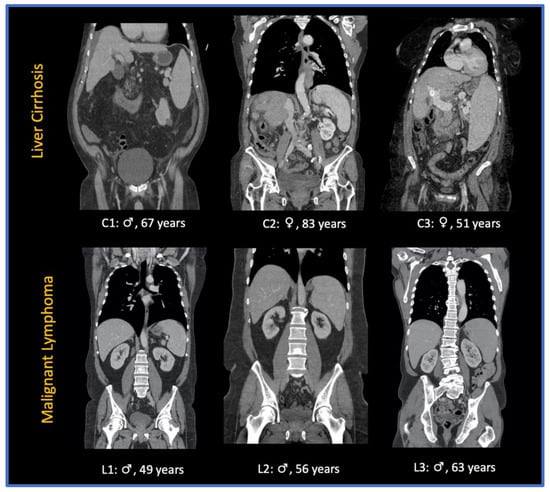

2.1. Study Population

3.1. Study Population